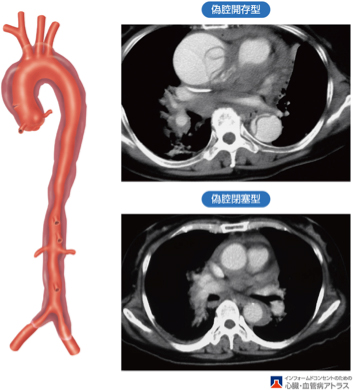

大動脈解離

大動脈解離とはどのような病気でしょうか?

大動脈壁に裂け目が入り、壁が2枚に分かれてしまう病気で、元々の血液の通り道(真腔)に加えて新しく通り道(偽腔)ができてしまいます。

大動脈解離に対する外科治療

心臓の近くまで大動脈が裂けてしまう(A型)と命に関わるため緊急手術が必要です【人工血管置換術】。

心臓から遠い大動脈しか裂けていないとき(B型)は血圧を厳重に管理する治療【降圧保存療法】となります。しかし、腹痛や下肢痛などの症状があるときは緊急手術【ステントグラフト内挿術】が必要です。